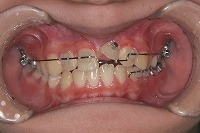

10歳4か月 | 10歳10か月 | 11歳1か月 | 11歳3ヵ月 | 11歳4か月 | 11歳7か月 | 11歳8か月 | |

反対咬合と前歯が生えてこない事を主訴に来院された、10歳4か月の男の子です。診断「下顎骨の過成長による骨格性反対咬合で上顎正中の左方偏位と埋伏歯を伴う」1期治療で反対咬合の解消と埋まっていた前歯を牽引しました。